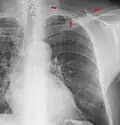

The supraclavicular fossa is an indentation (fossa) immediately above the clavicle.

Fullness in the supraclavicular fossa can be a sign of upper extremity deep venous thrombosis.